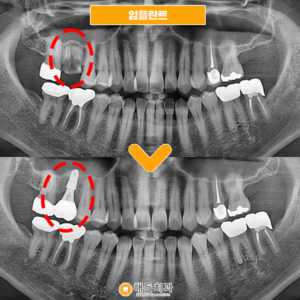

배방역치과 자연치아를 살리기 위해서는 (치료기간 : 2022.03~2022.06) 안녕하세요. 오늘은 저희 배방역치과를 내원하여 임플란트와 치관확장술을 통해 크라운치료하신 환자분을 소개해 드릴까 하는데요. 아래 사진을 보면서 설명해 드리도록 하겠습니다. 배방역치과 위 사진은 고*님의 치아 사진입니다. 고*님은 식사 때마다 통증을 느끼고 불편감을 느낀다고 하여 상담을 원한다고 하셔서 저희 치과에 내원해 주셨는데요, 더보기…